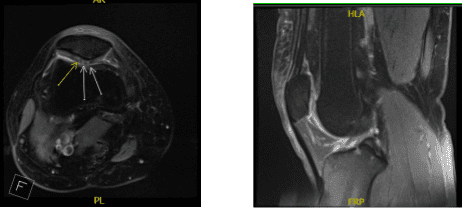

An MRI was done, which showed an osteochondral lesion in the patellofemoral joint. She had no relief with nonoperative treatment. We discussed treatment options and operative surgical management.

MRI Right knee non-contrast

Preoperative antibiotic was given. A lateral entry portal was made and an arthroscope was inserted. Examination showed grade 2 to grade 3 osteochondral lesions over the posterior surface of the patella. A medial entry portal was made with the use of a spinal needle.